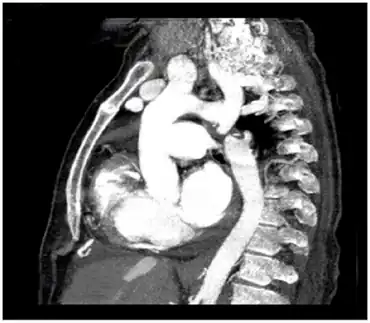

CT angiography showing type A interrupted aortic arch